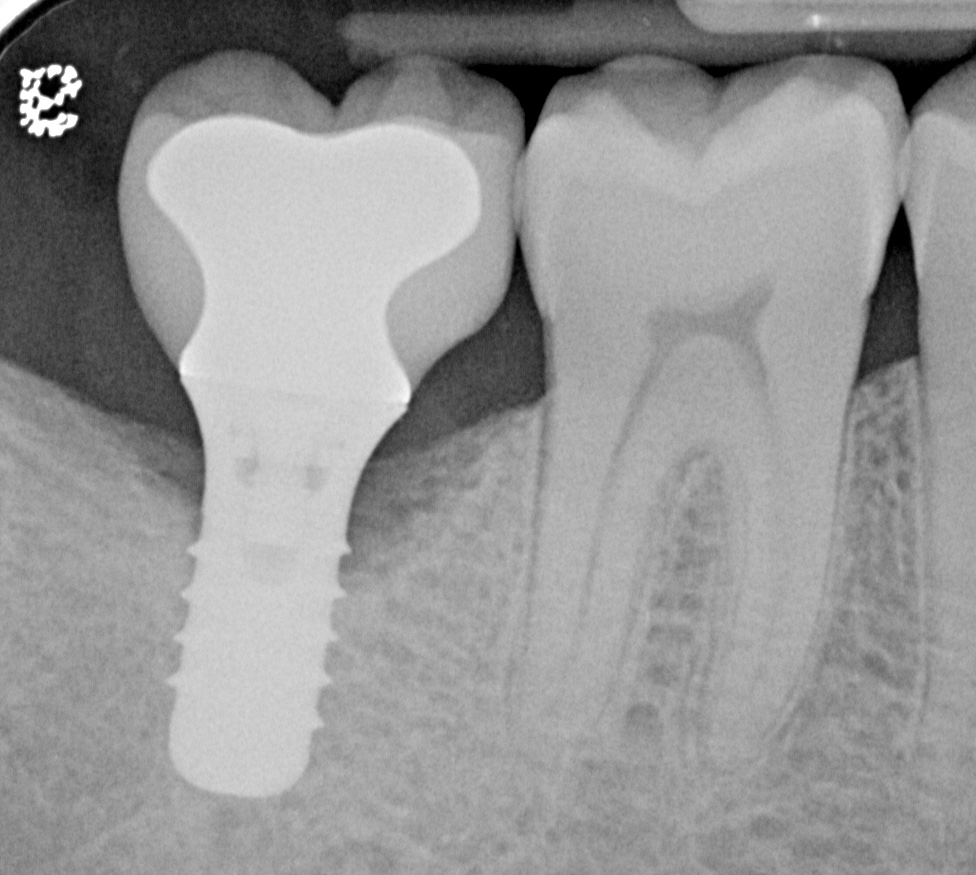

Fig 8. Radiograph taken 3 years after restoration of this mandibular right second molar implant demonstrating a peri-implant lesion.

Figure 8

Fig 11. Radiograph taken 1 year after regenerative therapy suggests favorable bone gain covering the entire roughened surface of the dental implant.

Figure 11